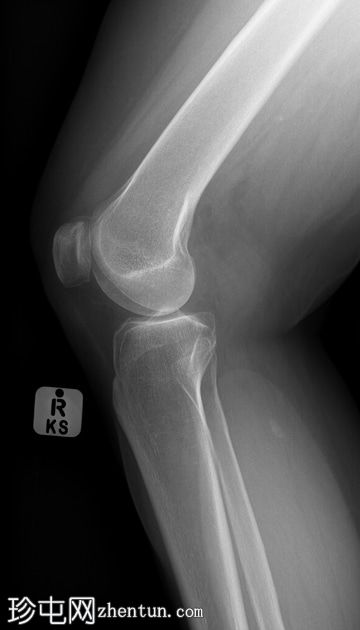

6.jpg

侧位片

PACS系统回顾显示既往右膝关节平片。可见内侧小腿植入物,在膝关节X线片上部分显影。正位片上易于识别,但在侧位片上可能被忽略,尤其是在缺乏病史的情况下。